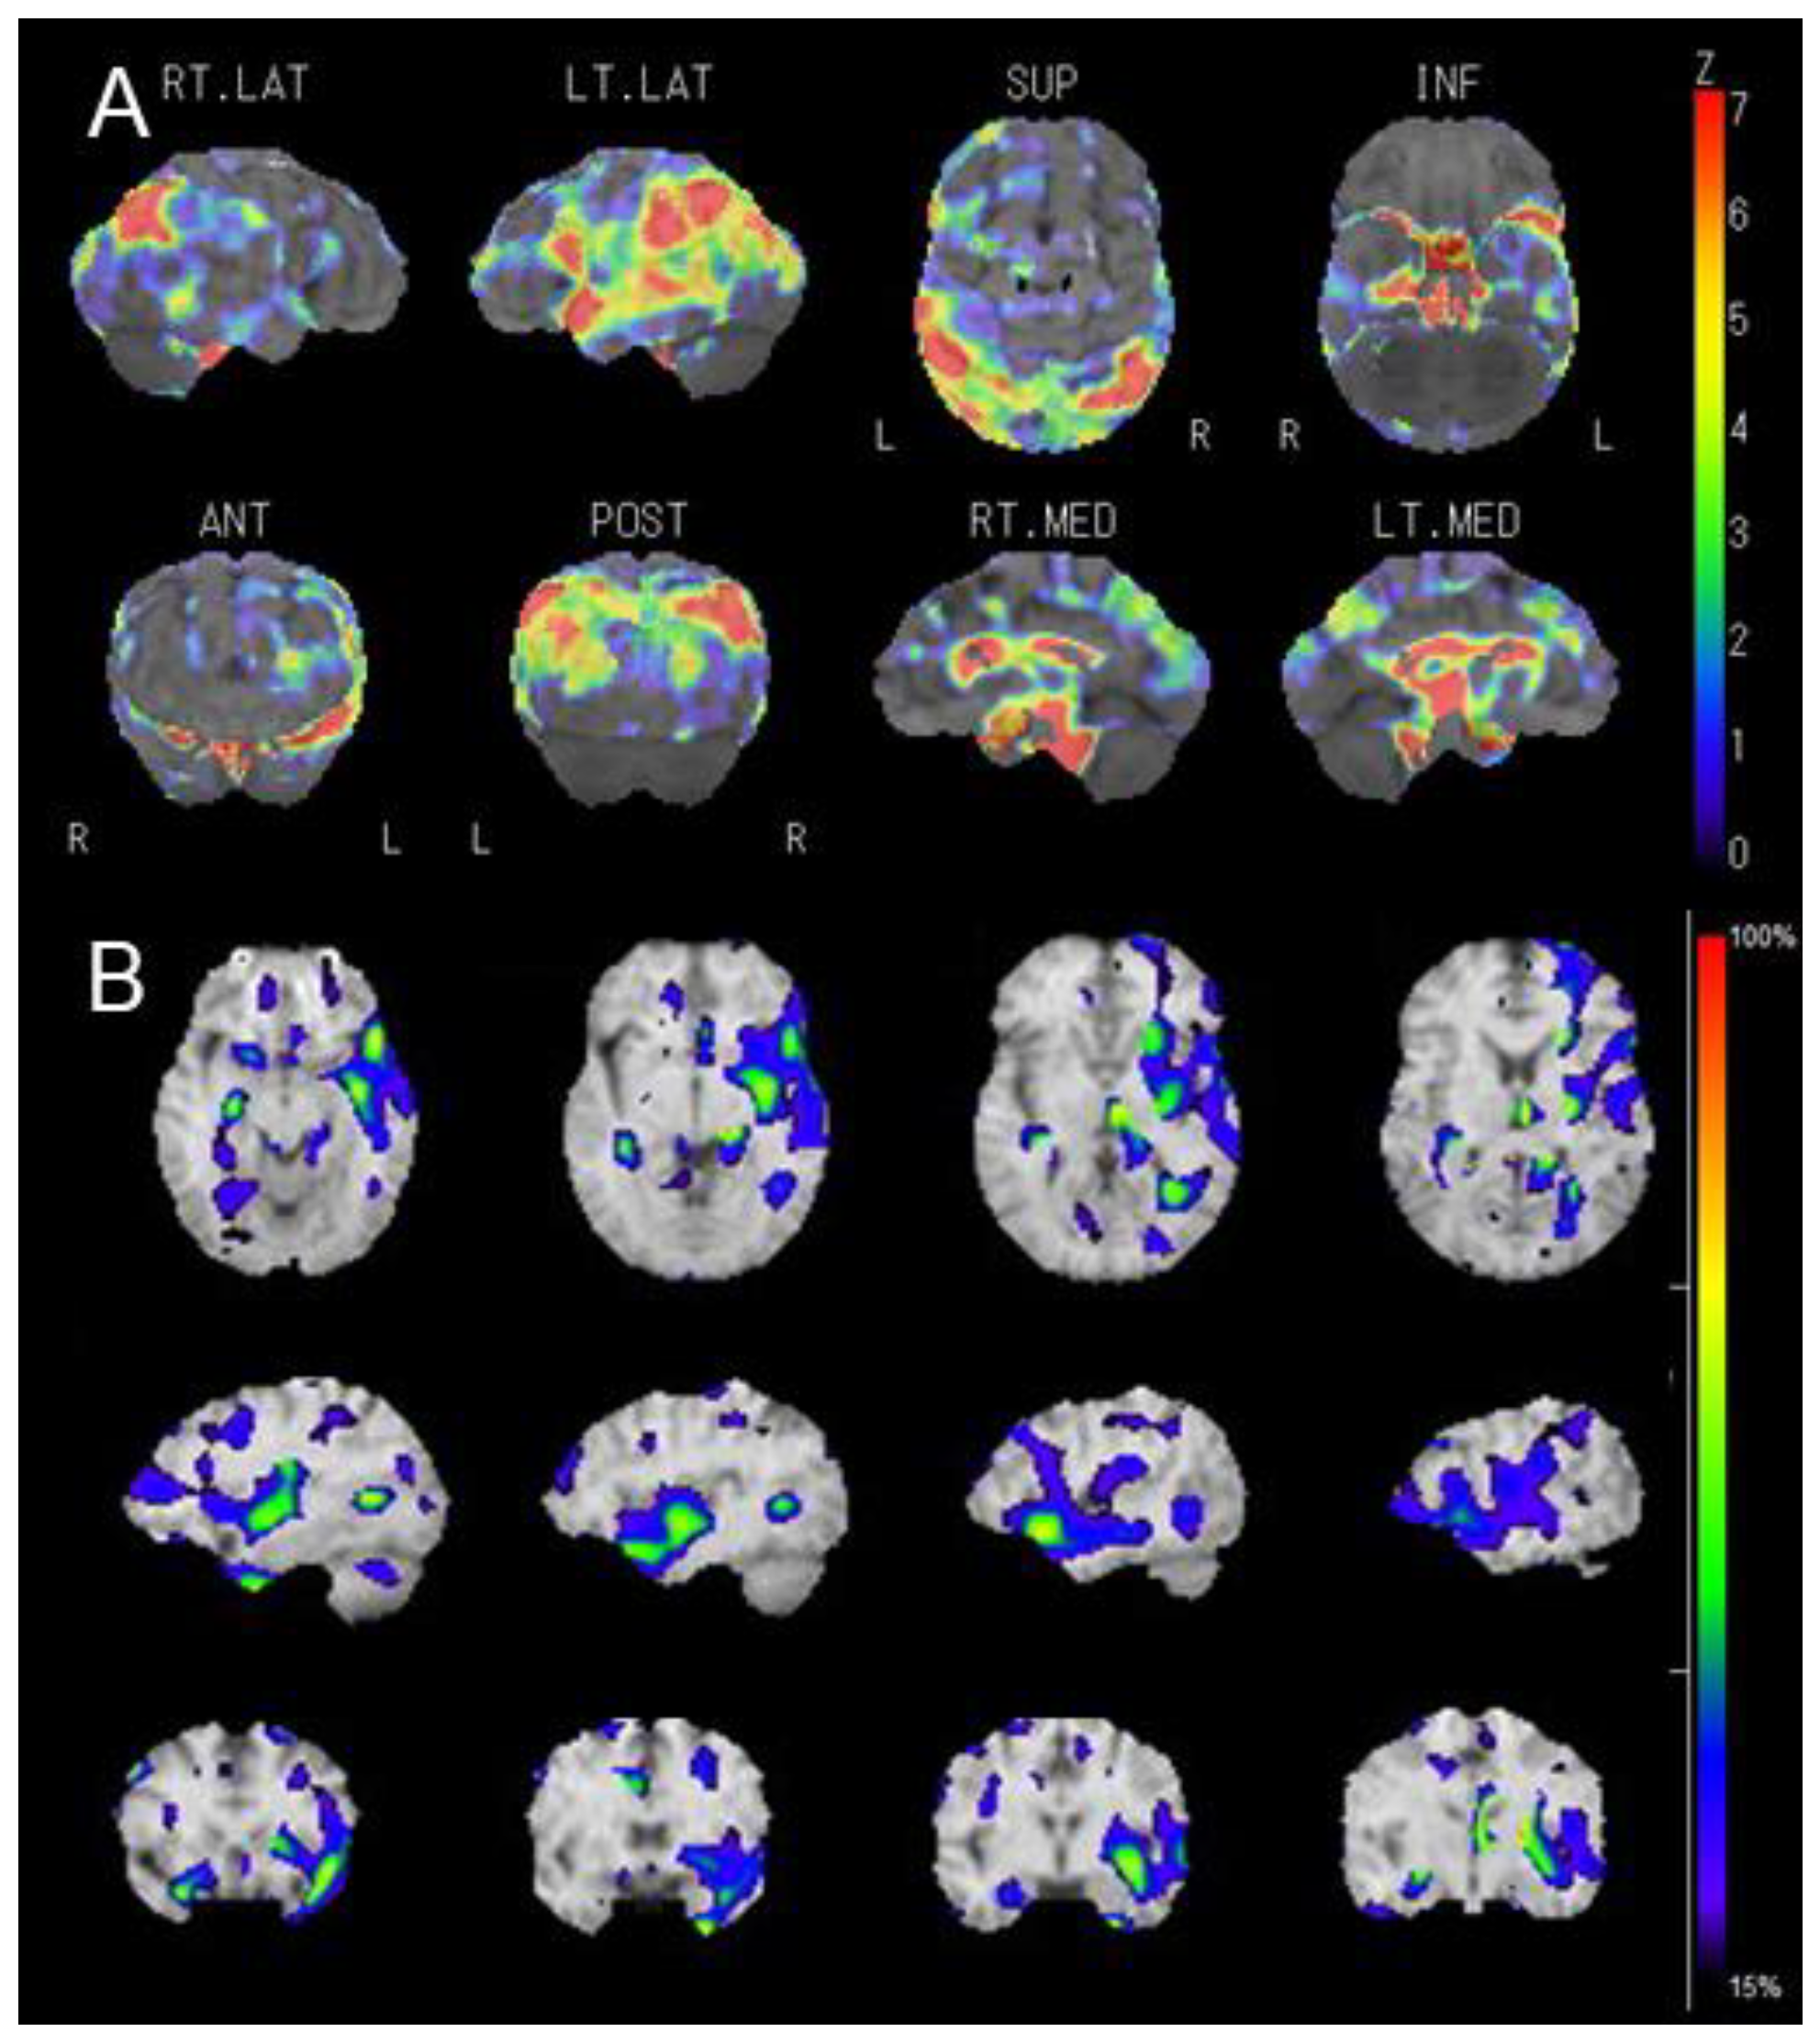

Diffusion MRI Fiber Tractography and Benzodiazepine SPECT Imaging for Assessing Neural Damage to the Language Centers in an Elderly Patient after Successful Reperfusion Therapy

2. Case Presentation